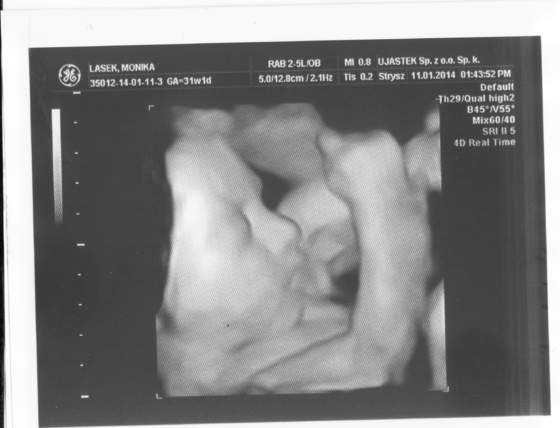

I wygralam tez USG 4D!!!!! Szkoda tylko, ze mojego meza nie było ze mna, bo był w pracy. Ale mamy teraz przynmajmniej jedno fajne zdjecie!

Dostalam tez dowod na zdjęciu, ze jest dziewczynka, chodz ja tam za duzo nie widze, ale lekarka tak twierdzi hehe ;-)